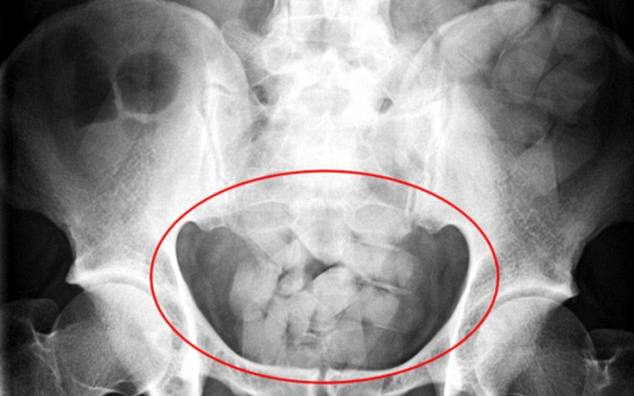

Mintegy 13 millió forint értékű kokainnal a gyomrában próbált meg bejutni az országba egy venezuelai nő, akit a NAV pénzügyőrei feltartóztattak a Liszt Ferenc-repülőtéren - közölte a NAV hétfőn az MTI-vel.

A közlemény szerint a budapesti repülőtérre egy Zürichen keresztül Sao Paulóból érkező venezuelai állampolgárt ellenőriztek a pénzügyőrök. Az utas a zöldfolyosón jelentkezett belépésre, azaz nem jelentett be semmilyen árut vámkezelésre, de az átvizsgálás során izzadt és remegett, így a pénzügyőrök feltételezték, hogy "kábítószernyelővel" van dolguk. A NAV munkatársai CT-vizsgálatra vitték, így derült ki, hogy a gyomrában 76 kapszulában 673 gramm kokain volt.

Fotó: illusztráció